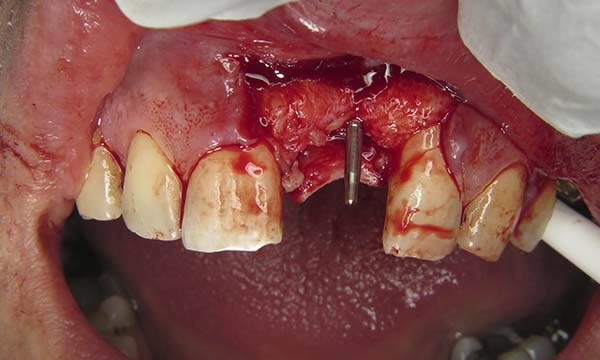

A case of a patient who was a long term resin retained bridge wearer. The resin retained bridge was placed after the patient lost his UL1 many years ago. There was a history of the resin retained bridge lute failing, and due to the loss of the UL1 there was a labio - palatal bone deficit.

A clear acrylic position guide was used to guide implant placement within the aesthetic envelope and guided bone regeneration was used labially to elevate the long standing concavity. A Bonded crown was used to restore the implant and at the 12 month follow up, the bone level around the implant remains unchanged and the patient is confidently smiling.

Case C

During Treatment